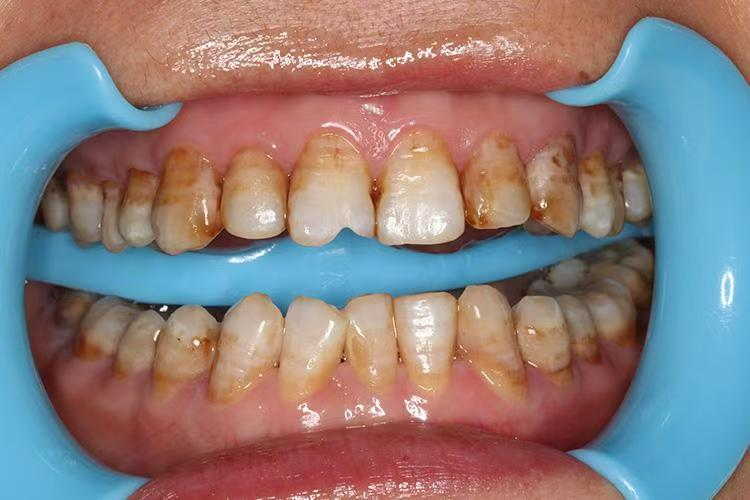

2.中度(着色型): 牙齿表面出现黄褐色或棕色的斑块,影响美观,但牙体形态没有明显缺损。

3.重度(缺损型): 除了严重的颜色改变,牙釉质还会出现凹凸不平的坑洼、缺损,甚至可能引发牙齿敏感。